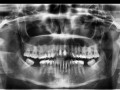

Jednostronne podniesienie zgryzu z zastosowaniem mostu…

Rozległa torbiel zawiązkowa żuchwy

Paulina Adamska, Maria Mikołajska, Anna Janowska, Anna Starzyńska